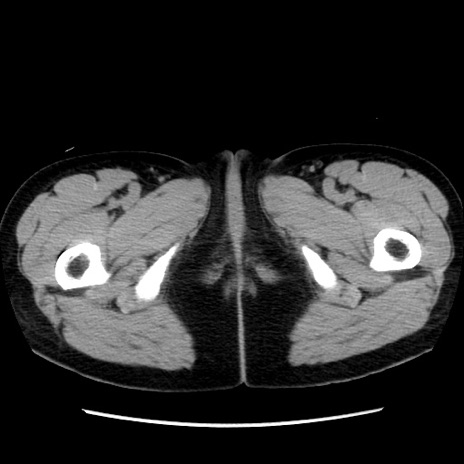

冠状断像